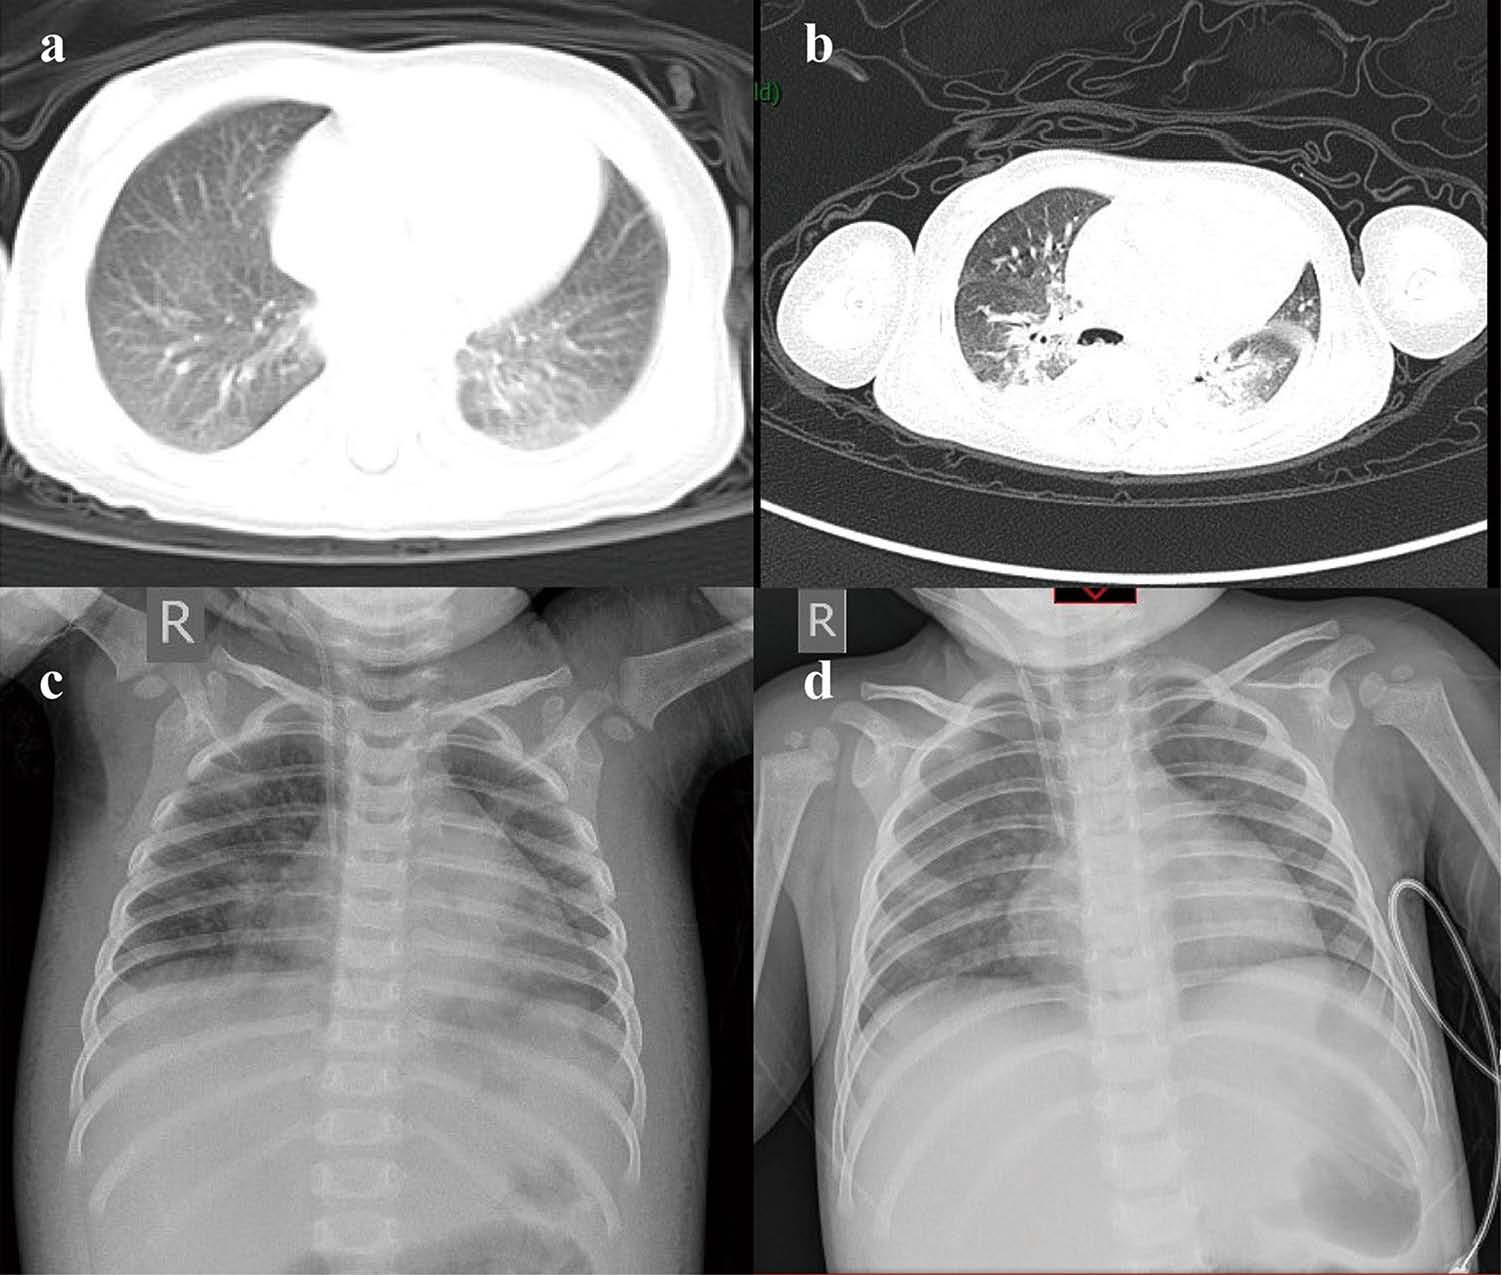

В статье Dan Sun et al. [26] приводится характеристика 8 тяжелых педиатрических пациентов с COVID-19 из Уханя (Китай). У этих пациентов наиболее распространенным симптомом были учащенное поверхностное дыхание, лихорадка и кашель. Характерными изменениями по данным рентгенологического исследования (обзорной рентгенографии грудной клетки и компьютерной томографии) были множественные очаговые затемнения и симптом «матового стекла». У всех критических пациентов были признаки цитокинового «шторма». В качестве иллюстрации типичных изменений приводим клинический пример ребенка первого года жизни с инфекцией COVID-19 и двусторонней пневмонией (рисунок).

Рис. Больной 10-месячный мальчик с инфекцией COVID19 и двусторонней пневмонией, контактировавший с заболевшей матерью. Клинические проявления: одышка, кашель, большое количество мокроты, рвота. В легких при аускультации определялась крепитация. Находился на ИВЛ в течение 7 дней. Рентгенография грудной клетки и КТ грудной клетки: а – небольшие плотные тени и выпот в плевральной полости (4 февраля 2020 г.); b – симптом «матового стекла» и очаги инфильтрации (9 февраля); с – развитие поражения (12 февраля); d – рентгенография грудной клетки с улучшением (в динамике) [26]